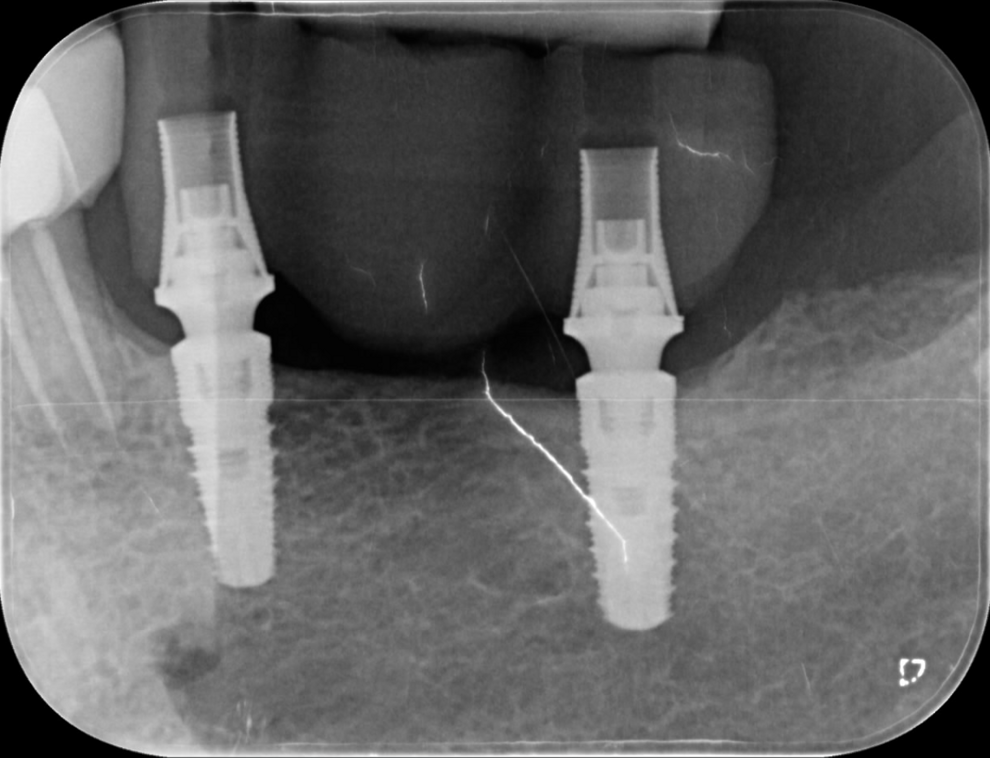

Once screwed to the implants, the prosthesis demonstrated excellent stability and seamless integration with the peri-implant tissue (Fig. 12). No occlusal retouching was performed.

Fig. 12: Bridge in position on the implants, demonstrating seamless integration with the peri-implant bone.